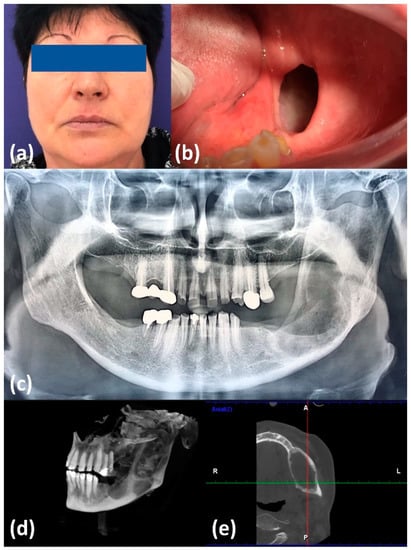

2. Case Report